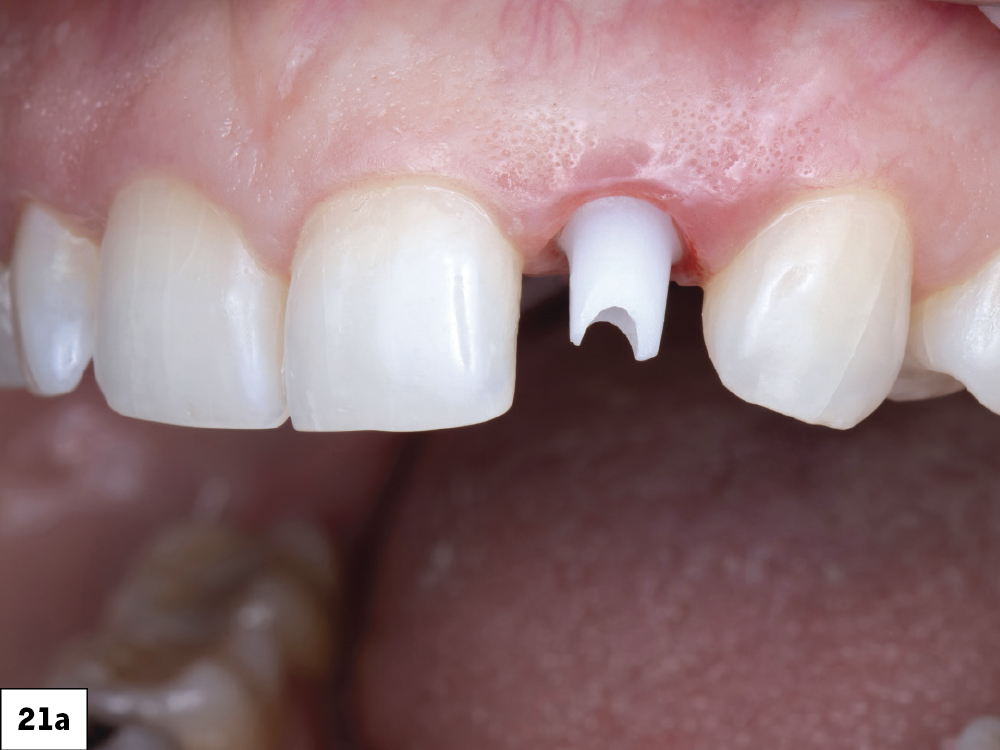

Figures 21a, 21b: The abutment was tried in to verify the marginal position and then hand-tightened into place. An X-ray was then taken to ensure the abutment was fully seated. Because a 3.0 mm Glidewell HT implant was placed, the abutment was torqued to 15 Ncm.